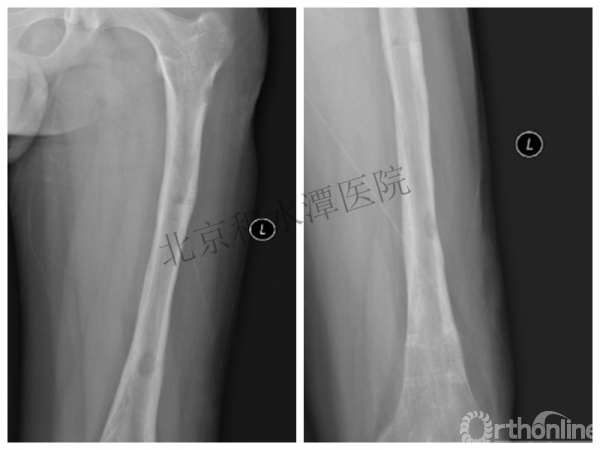

又过了4年!时间来到2015年

一年以后顺利愈合,实则危机四伏

数月后再骨折!牵引!

髋人字支具

外固定架术后一年

整整11年!是否治疗终结?

病人的付出?医生当反思!